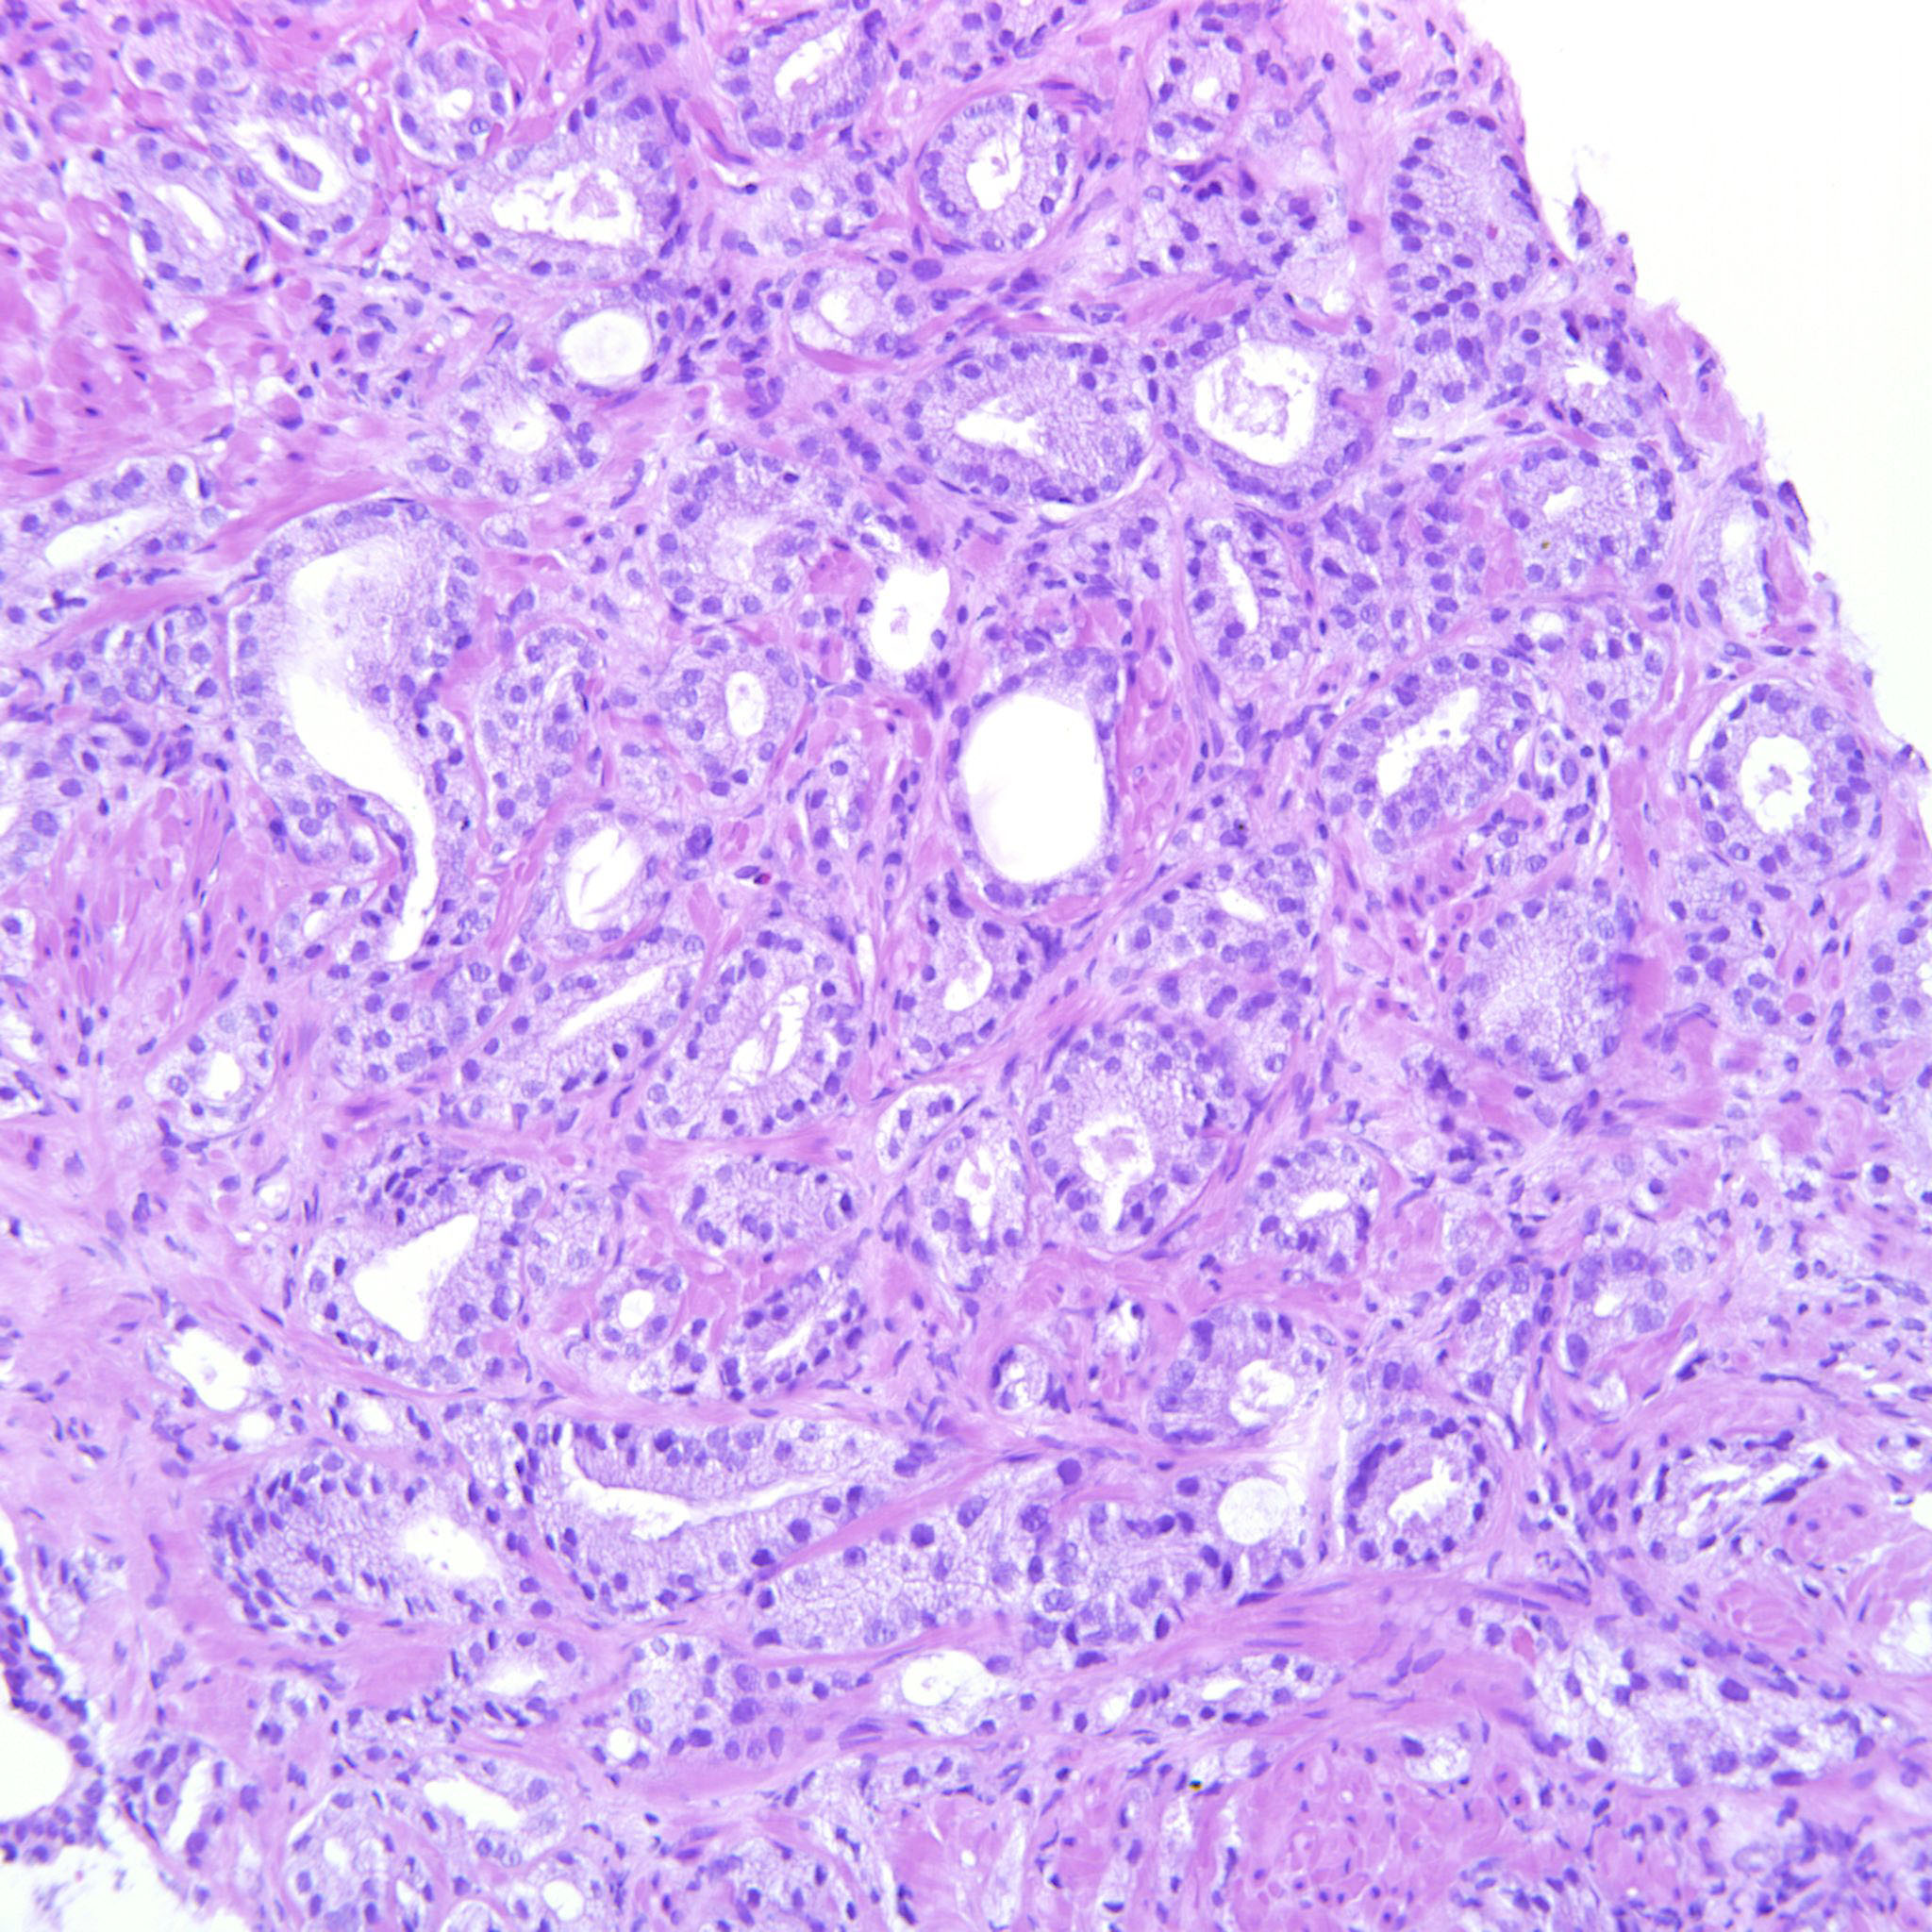

Prostate cancer grading

Case ID: 122